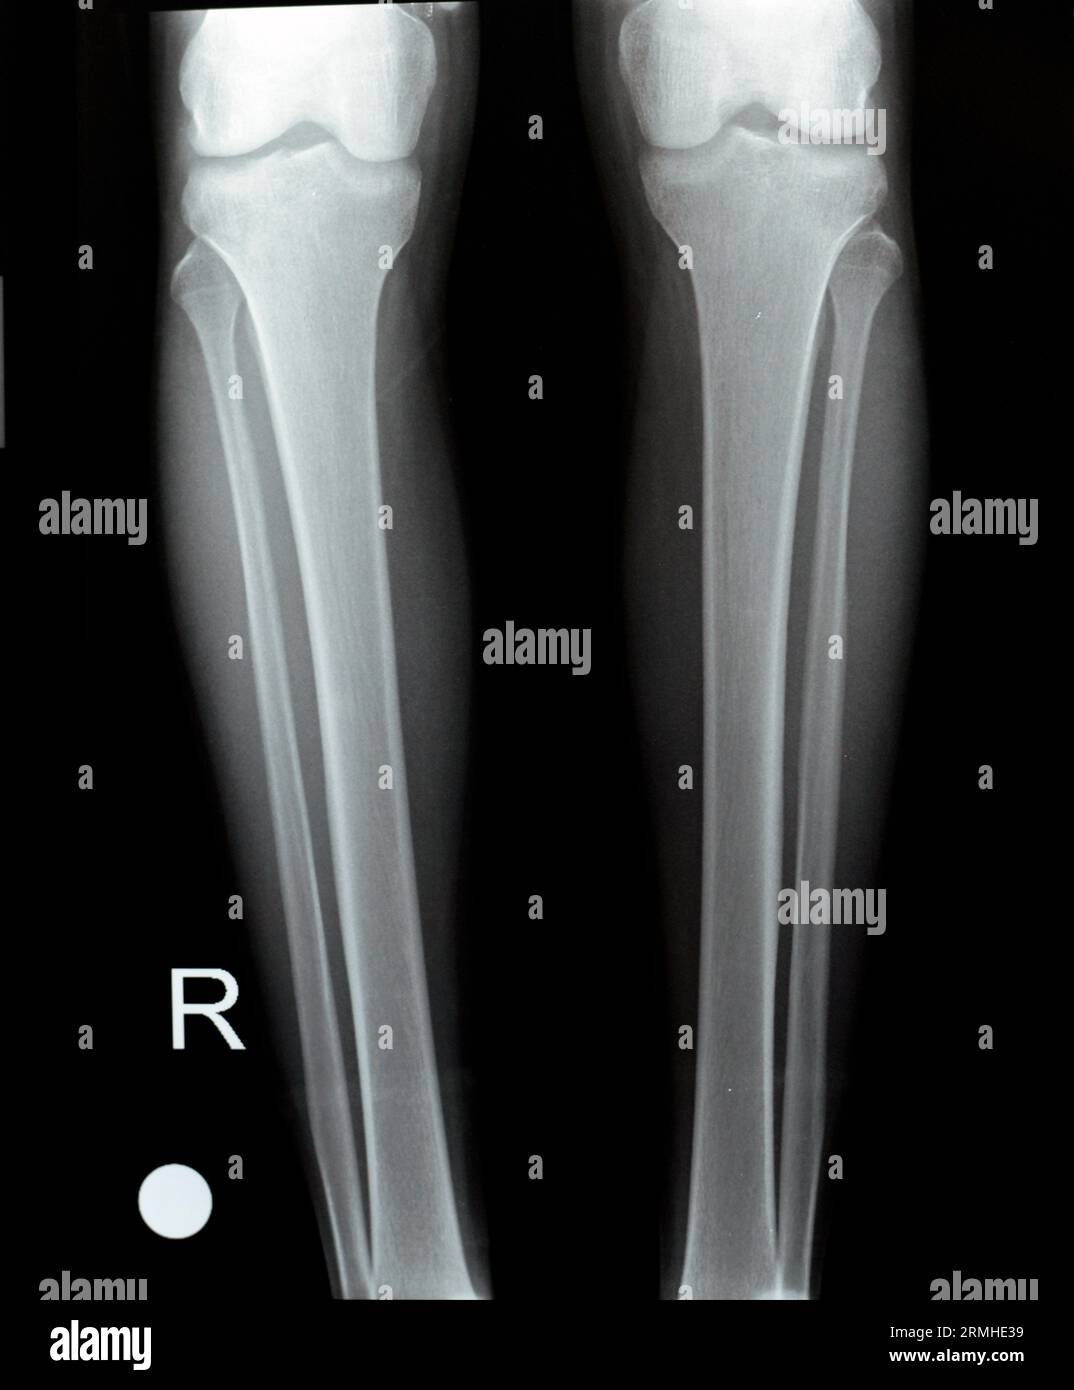

Normal Knee X Ray 13 Year Old - Normal appearances of the knee joint in the growing patient. Web this is a repository of normal pediatric bone xrays and their examples for a quick reference look. It can show broken bones or a dislocated joint. Web normal ap and lateral knee radiographs in an adult male for reference. This article lists examples of normal imaging of the pediatric.

Normal Knee X Ray 13 Year Old - Web normal ap and lateral knee radiographs in an adult male for reference. Citation, doi, disclosures and article data. It can show broken bones or a dislocated joint. Web database of reference normal pediatric imaging including normal pediatric radiographs, cts, and mris by child age from birth to age 16. Web this is a repository of normal pediatric bone xrays.

Normal Knee X Ray 13 Year Old - Web database of reference normal pediatric imaging including normal pediatric radiographs, cts, and mris by child age from birth to age 16. Citation, doi, disclosures and article data. Web normal ap and lateral knee radiographs in an adult male for reference. It can show broken bones or a dislocated joint. Normal appearances of the knee joint in the growing patient.